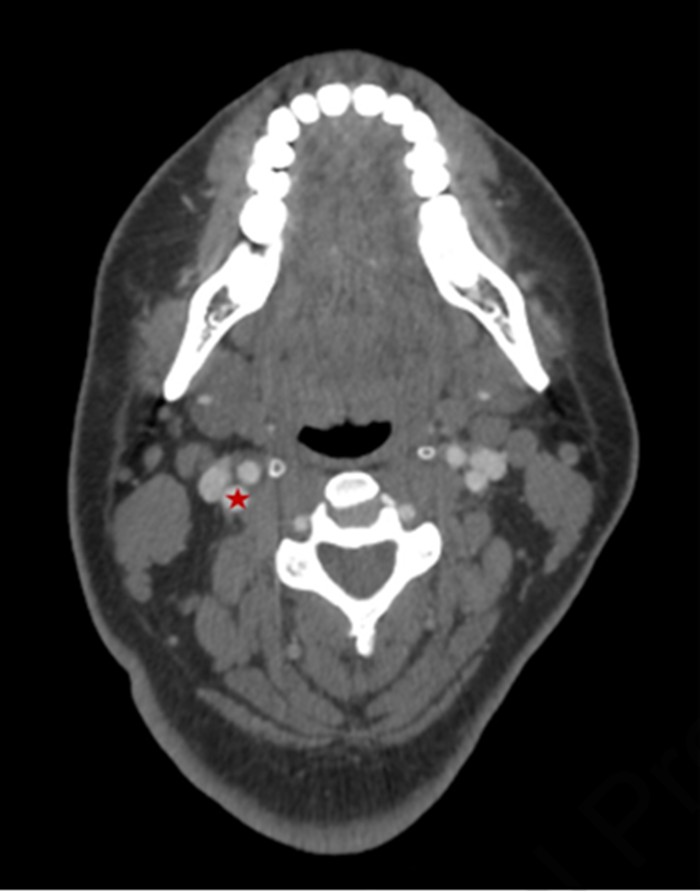

Shortly afterward, the patient developed expressive aphasia and left-sided weakness. Emergency imaging confirmed a right middle cerebral artery (MCA) infarction, with radiopaque material consistent with CaHA filler visible in the MCA (Figure 3). Given the proximity of the ICA to the intended injection site, the embolic event was attributed to inadvertent intravascular injection into the ICA. This case represents a severe form of calcium hydroxyapatite filler side effects, specifically a vascular complication.

Figure 3:Coronal reconstruction of a non-contrast head CT scan showing radiopaque calcium hydroxyapatite (CaHA) material within the middle cerebral artery (MCA, highlighted in red box), resulting in sequelae of acute infarction in the right cerebral hemisphere.

In the supine position, with skin laxity and tissue displacement, the ICA may lie as close as 4 cm beneath the skin surface over the mandibular angle (Figure 4). Deep injections, combined with external pressure on the skin, may inadvertently allow a needle to reach the ICA.

Figure 4: Axial contrast-enhanced CT of the neck demonstrating the internal carotid artery (ICA, marked with a red star) located approximately 4 cm beneath the skin surface at the deep aspect of the right mandibular angle.